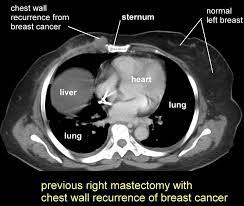

A total body ct scan generally includes at least the chest, abdomen, and pelvis. In women with breast cancer, this test is most often used to look at the chest and/or abdomen to see if the cancer has spread to other organs. A ct scan can be wrong: However, multidetector computed tomography (ct) often provides the first images of the breast when scanning is performed for pulmonary or cardiac disease. It feels like about an inch around, like the size of a big marble. The contrast helps to show up areas of increased vascularity and so it does help show up tumours as they have a rich blood supply. It can show metastatic colon cancer that has spread to the liver. Doctors often use this is for cancer staging. A sentinel lymph node biopsy may first be performed to determine whether cancer has spread to the lymph glands under the arm. Some researchers are studying the usefulness of pet (positron emission tomography)/ct scans in staging inflammatory breast cancer. Mammography is currently the preferred examination for breast cancer screening; Lobular breast cancer can be more difficult to see on imaging and scans. Right now, ct scans are not used routinely to evaluate the breast.

Other names for this test: This test is most often used to look at the chest and/or belly (abdomen) to see if breast cancer has spread to other organs. Before any pictures are taken, you may be asked to drink 1 to 2 pints of a liquid called oral contrast. As radiologists, we follow a measure called as low as reasonably achievable. this means we give enough radiation to create ct images that are of high enough quality that we can make a good clinical decision, but we keep the radiation as low as. It feels like about an inch around, like the size of a big marble.

Identifying Bone Metastases Radiology Key from radiologykey.com When a breast cancer has been diagnosed, some people have a ct scan of their chest and tummy (abdomen) to stage the breast cancer. This test is most often used to look at the chest and/or belly (abdomen) to see if breast cancer has spread to other organs. Lobular breast cancer can be more difficult to see on imaging and scans. It can damage the dna in your cells and raise the chance that they'll turn cancerous. A chest ct scan can detect even smaller nodules in the lung. Binderow continues, ct is very good for solid organ disease — liver, spleen, kidneys. Learn more about it on our blog. Computed tomography scan, ct scan, cat scan, and spiral or helical ct a ct scan can help doctors find cancer and show things like a tumor's shape and size.